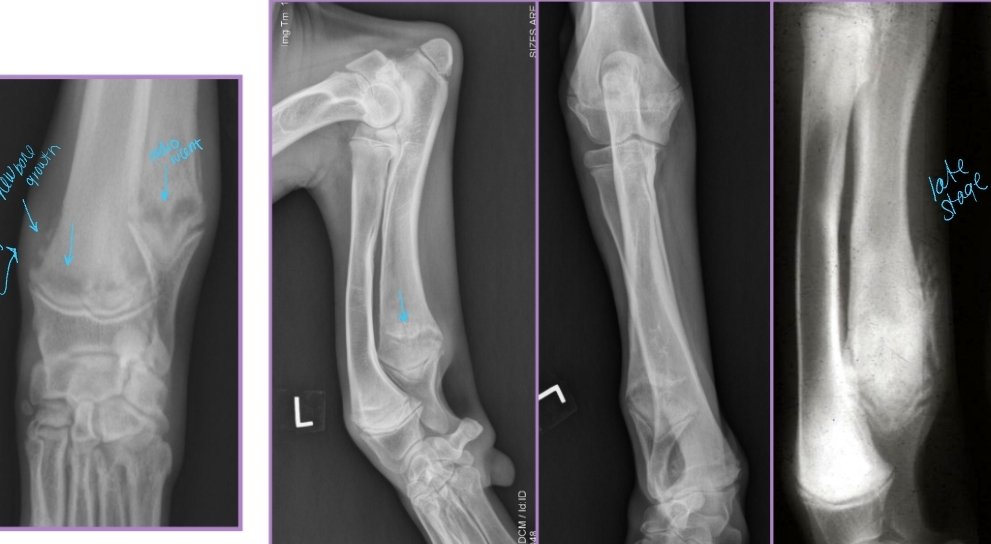

Panosteitis

Et: Disease of endosteum and bone marrow in the long bones

Increased IO pressure due to protein accumulation near nutrient foramen (near major BV), medullary vessels leakage

ulna, humerus, radius, femur, tibia

Forelimb > hindlimb

Sig: 5-18 months, male > female, large breed

Cs: Shifting leg lameness, Lethargic, Pain (cyclic), Anorexia, Fever

Dt:

PE: pain on palpation of diaphysis of long bone

pain receptors in periosteum

Radiographs: Radiodense, patchy infiltrates, Widening of nutrient foramen

Late periosteal response – smooth, thick cortex appearance

Tx: Analgesics, Rest, Self-limiting (1-2w)

relapse can present in other bones

Hypertrophic Osteodystrophy (HOD)

AKA: Scurvy, Moeller-Barlow disease, Metaphyseal osteopathy, Osteodystrophy type I & II, Hypovitaminosis C

Et: Disease of long bones, especially distal metaphyses

Capillary loops become necrotic, vascular congestion, edema, metaplastic cartilage/bone

Forelimbs > hindlimbs

Sig: Juvenile large breed dogs, Rapid growth, <12 months

Cs: Acute onset of lameness, Fever, Lethargy, Anorexia, Diarrhea, Pain at metaphyses, Heat at metaphysis on all 4 limbs!!

Dt: Radiographs

Irregular, radiolucent line in metaphysis adjacent/parallel to physis (“double physeal line”)

Metaphyseal flaring + sclerosis

Subperiosteal and extraperiosteal new bone formation

Tx: Analgesics, antibiotics,self-limiting